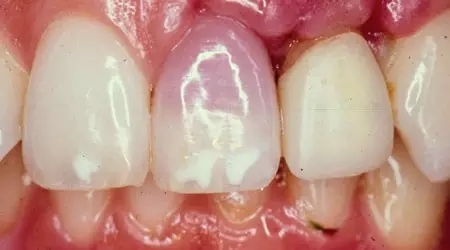

牙齒變暗、發(fā)黑

8.webp.jpg

牙齒外傷后顏色改變可能有兩點原因:要么是為了保護(hù)神經(jīng),要么是已經(jīng)死了。

如果是保護(hù)神經(jīng),牙齒可能比鄰牙看起來暗一點。如果像挫傷一樣改變顏色(從粉紅到灰白),意味著牙齒很有可能死亡,可能需要根管治療后冠修復(fù)治療。在某些情況下,可能需要拔除牙齒。如果是乳牙,可以不用管,直到脫落。